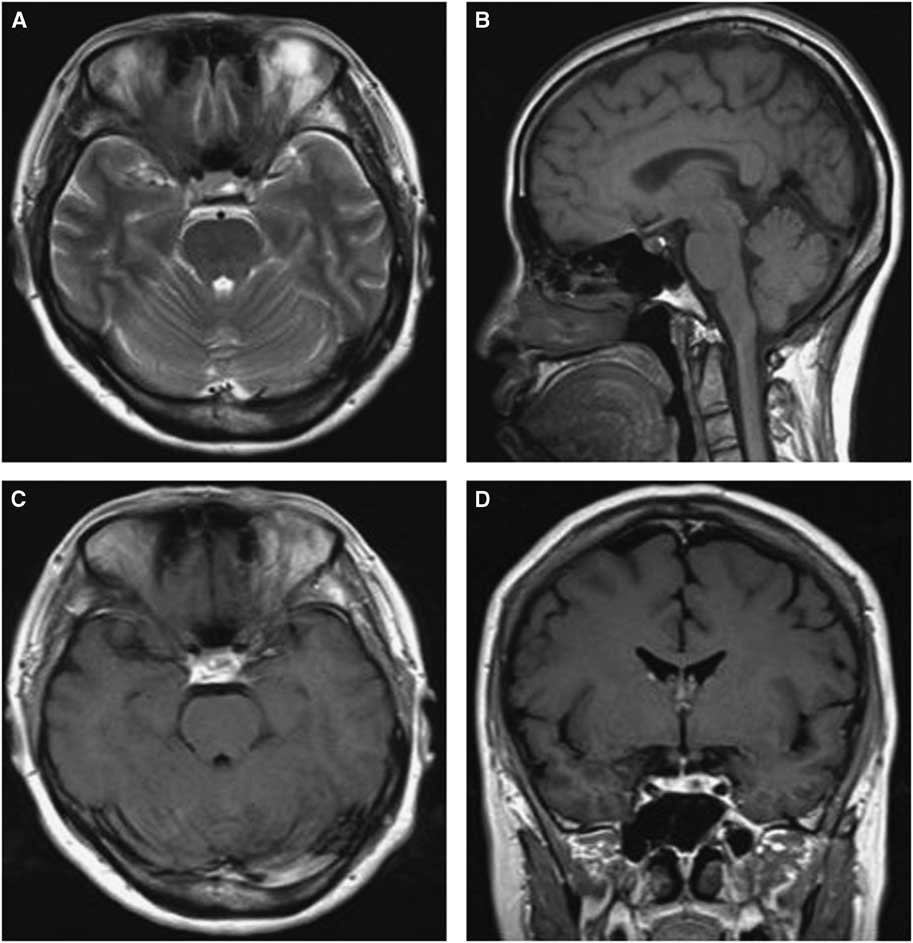

Microscopically, the tumor contained two components. The first component was monomorphic cells with round or oval nuclei containing stippled chromatin. The second component showed fragments of a cyst wall lined by simple cuboidal or pseudostratified ciliated columnar epithelium; the lumen of the cyst contained an abundance of myxoid materials (Figure 3A). Immunohistochemical analysis demonstrated positive results for PRL and GH/PRL in three patients (Figure 3B-C). A positive result for GH staining was indicated in one patient. There was no obvious staining in the other five cases, which were diagnosed as nonfunctional PAs (NFPAs) associated with RCC. Additionally, positive expression of cytokeratin in 8/18 cases was observed.

Figure 3 Hematoxylin-eosin and immunohistochemical findings for case 12. (A) Clusters of uniform PA cells with mucin-filled cyst. The cyst was lined by ciliated columnar epithelium (×200). (B) Immunostaining of GH was positive in the adenoma cells (×200). (C) PRL staining of adenoma cells showed strong reactivity (×200).